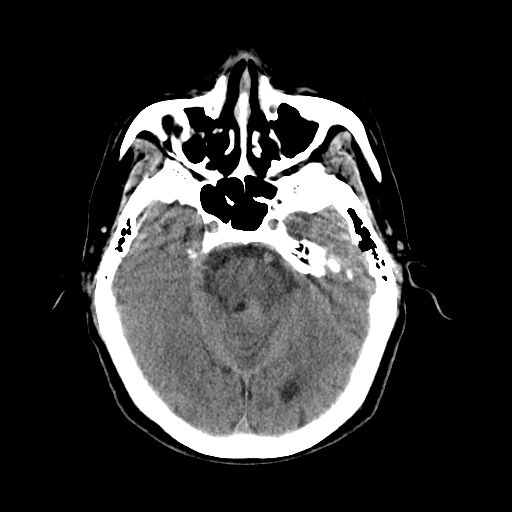

以下是引用dsl555在2008-11-11 18:52:00的发言:[br]四脑室后上方,四叠体池上方可见一小结节状稍高等密度影,比40天略大,建议mri或增强

以下是引用zjzjr在2008-11-12 8:28:00的发言:[br]四脑室后方略高密度影,周围环一低密度水肿带,四脑室受压变形,考虑小脑蚓部血肿吸收期或占位,建议增强